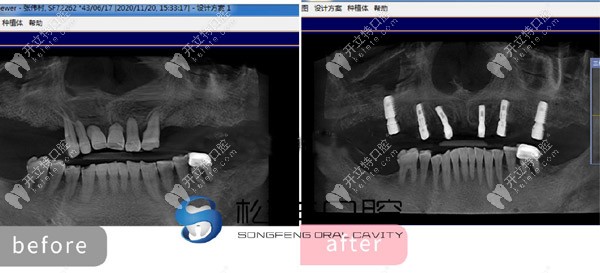

★ 顧客下頜多顆缺失,

上海松豐齒科的蔣院長(zhǎng)采用了即刻種植技術(shù),讓顧客當(dāng)天就了下半口牙。

下頜即刻種植